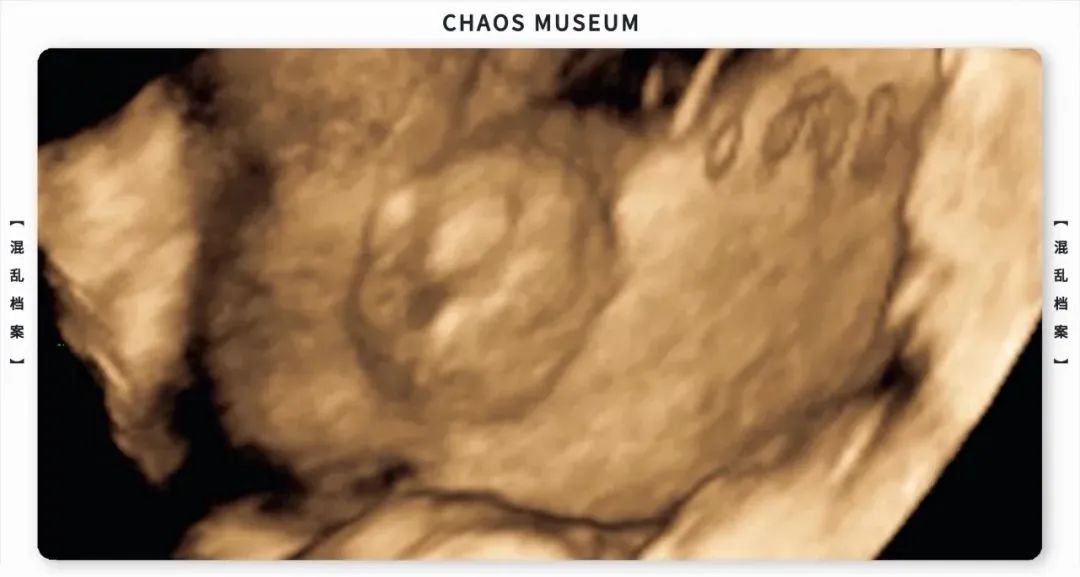

比如最重要的,讓胎兒(Fetus)發育出男性生殖器(性分化),讓男孩長出喉結和鬍子(第二性徵),或者影響蛋白質合成的效率,抑制分解代謝,促進骨骼肌的生長。